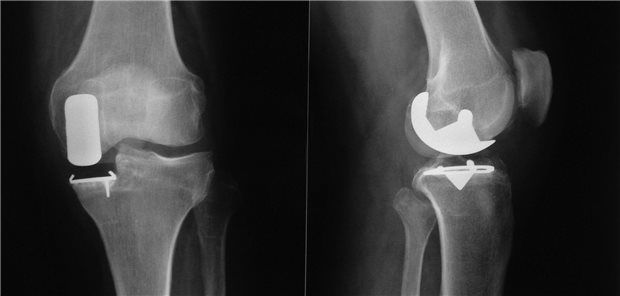

Die unikompartimentelle Knieprothese ist dem primären Totalersatz des Kniegelenks offenbar auch dann nicht unterlegen, wenn ein Revisionseingriff mit Wechsel zur Knie-TEP erforderlich wird.